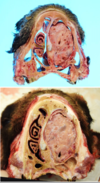

Q

This is a picture of a rumen. What lesion is shown here?

A

Acute, multifocal to coalescing ulcerative ruminitis